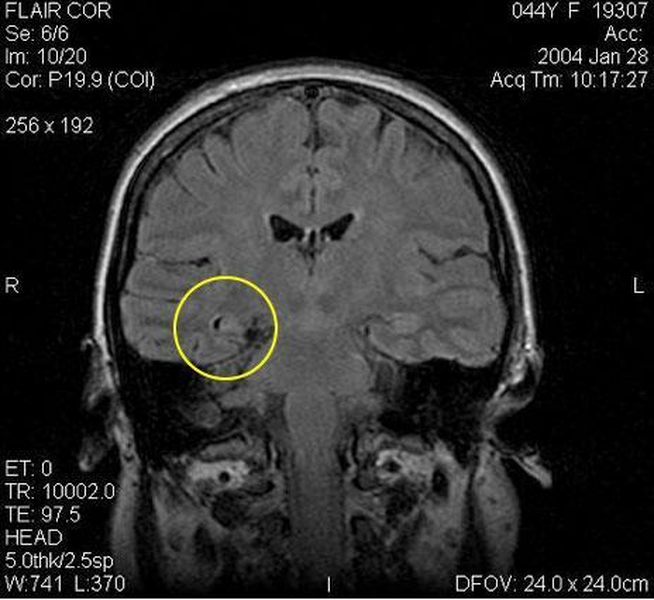

Эпилепсия височной доли

Эпилепсия височной доли 115 фотографий